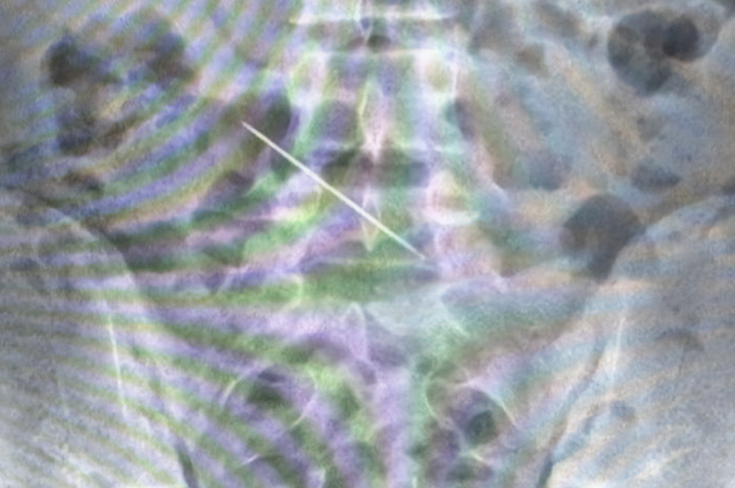

13-летнему школьнику провели инструментальное исследование, в ходе которого стало ясно, что причиной боли является невоспалительное поражение аппендикса — на рентгеновском снимке врачи увидели в брюшной полости большую швейную иглу.

Длина иглы составила 5 см, она застряла в поперечной ободочной кишке и проткнула ее. При этом ребенок не смог вспомнить, при каких обстоятельствах иголка оказалась внутри его организма.